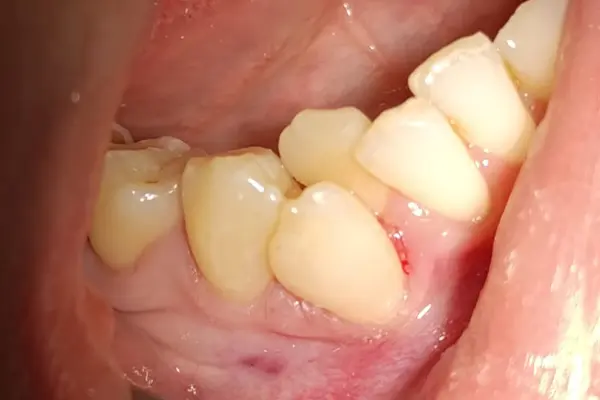

Виталий Лаврысь: “43, 44 зубы, кариес дентина, вестибулярная полость”

В этом клиническом случаем от Виталия Семёновича Лаврысь мы рассмотрим лечение кариеса дентина 43 и 44 зуба с использованием композитов B&E.

На первом фото - сразу после полировки, на втором через два дня.

Обратите внимание, что материал «схамелеонил»! Эффект «хамелеона» достигается при правильной «игре» с оттенками дентинных и «боди» по толщине. По консистенции и оптическим свойствам материалы B&E ближе к композитам Gradia Direct (GC, Япония). Это показывает, что при правильном подходе можно добиться очень естественного и эстетичного результата, который меняется в зависимости от освещения и угла зрения.